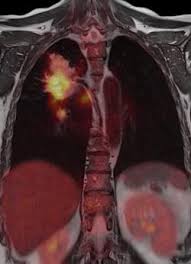

Clinical applications of PET/MR: current status and future perspectives.

PET-MRFully integrated positron emission tomography (PET)/magnetic resonance imaging (MRI) scanners have been available for a few years. Since then, the numbers of scanner installations and published studies have been growing. While feasibility of integrated PET/MRI has been demonstrated for many clinical and preclinical imaging applications, now those applications where PET/MRI provides a clear benefit in comparison to the established reference standards need to be identified.

The current data show that those particular applications demanding multiparametric imaging capabilities, high soft tissue contrast and/or lower radiation dose seem to benefit from this novel hybrid modality. Promising results have been obtained in whole-body cancer staging in non-small cell lung cancer and multiparametric tumor imaging. Furthermore, integrated PET/MRI appears to have added value in oncologic applications requiring high soft tissue contrast such as assessment of liver metastases of neuroendocrine tumors or prostate cancer imaging. Potential benefit of integrated PET/MRI has also been demonstrated for cardiac (i.e., myocardial viability, cardiac sarcoidosis) and brain (i.e., glioma grading, Alzheimer's disease) imaging, where MRI is the predominant modality. The lower radiation dose compared to PET/computed tomography will be particularly valuable in the imaging of young patients with potentially curable diseases. However, further clinical studies and technical innovation on scanner hard- and software are needed. Also, agreements on adequate refunding of PET/MRI examinations need to be reached.

Finally, the translation of new PET tracers from preclinical evaluation into clinical applications is expected to foster the entire field of hybrid PET imaging, including PET/MRI.